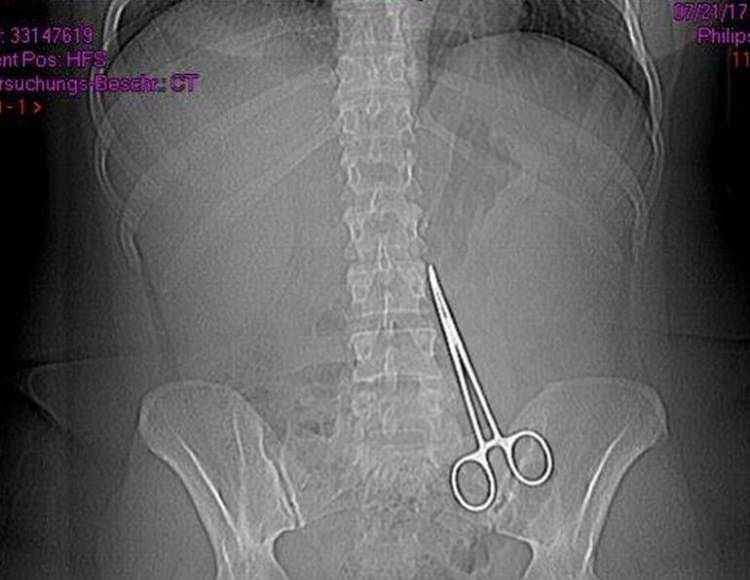

Zamanla karnında şişlikler oluşan, ağrı çeken ve hareket etmekte zorlanan Bingöl'ün, Almanya'daki bir hastanede çektirdiği röntgende karnında makas olduğu tespit edildi.

Bu nedenle psikolojik sorunlar da yaşayan Bingöl'ün, geldiği Şanlıurfa'da özel bir hastanede gerçekleştirilen ameliyatla karnındaki makas alındı. Bingöl, avukatı Şiyar Yıldırım aracığıyla "Hizmet kusuruna dayalı işlem sebebiyle maddi ve manevi zararın ödenmesi" talebiyle estetik ameliyatı gerçekleştiren doktor ve hastane hakkında dava açtı.

"Karnımın sol tarafı iki yumurta büyüklüğünde şişti, eğrilip doğrulamadım, evimi temizleyemedim, işimden oldum. Sürekli doktorumla yazıştım, şikayetlerimi ve fotoğraflarımı ilettim. Kendisi 'Bunlar zamanla geçer, zaten Türkiye'ye onuncu ayda tatile geleceksin, o zaman muayene ederim seni, her şey yoluna girer, sıvı birikmiştir, geçer kendini sıkma sürekli, masaj yap.' dedi. Sürekli masaj yaptım ama baktım olmayınca Almanya'da doktora gittim. Çekilen renkli röntgende karnımda makas olduğunu söylediler. Ben 2-3 saat kendime gelemedim, şok geçirdim. Ailece ne yapacağımızı şaşırdık."

Bingöl, röntgenini ulaştırdığı Gaziantep'teki doktoru N.G.Ö'nün "Üzgün olduğunu ve hemşirenin hata yaptığını, kendisini tekrar ameliyat ederek, makası alabileceğini" söylediğini öne sürdü. Çocuklarının bu tür olayların filmlerde olduğunu sandığını dile getiren Bingöl, konuyla ilgili hukuki işlem başlattığını, avukatı Şiyar Yıldırım'ın gerekli yasal prosedürü takip ettiğini bildirdi.